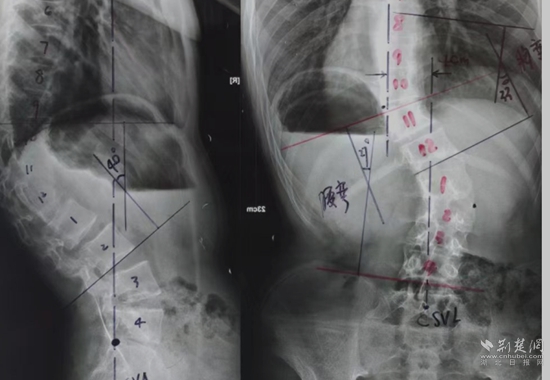

全脊柱X光檢查。通訊員 供圖

余國慶醫(yī)生檢查后發(fā)現(xiàn),這名患者全身皮膚長滿咖啡色的斑塊和瘤狀的突起,身體極為消瘦,骨架突出后可以看到明顯的駝背、剃刀背及側彎畸形。結合隨后的全脊柱X光檢查,確診這是一例少見的神經(jīng)纖維瘤病性脊柱側后凸畸形患者。余醫(yī)生當即將這名患者收住院治療。